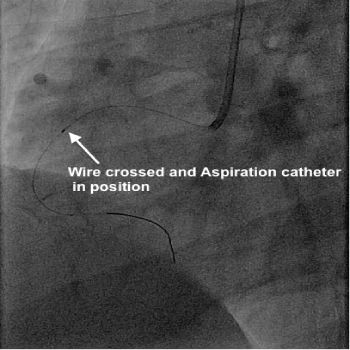

Her coronary angiogram, which was performed via right radial approach showed a totally blocked artery (right coronary artery) with plenty of thrombus, as expected. It was decided to perform angioplasty and therefore a wire was passed to cross the occlusion, which was successful. Then a thrombus aspiration catheter was inserted into the RCA, and a long serpentine clot was removed from the RCA. Further to this blood flow was established in the RCA, which showed a long segment of underlying narrowing of 70%. An OCT (optical coherence tomography) catheter was passed to assess the narrowing and size of the artery to decide about the stent. Then a drug coated stent was deployed in the narrowing to remove the block which was successful. This established a normal and brisk flow in the artery.